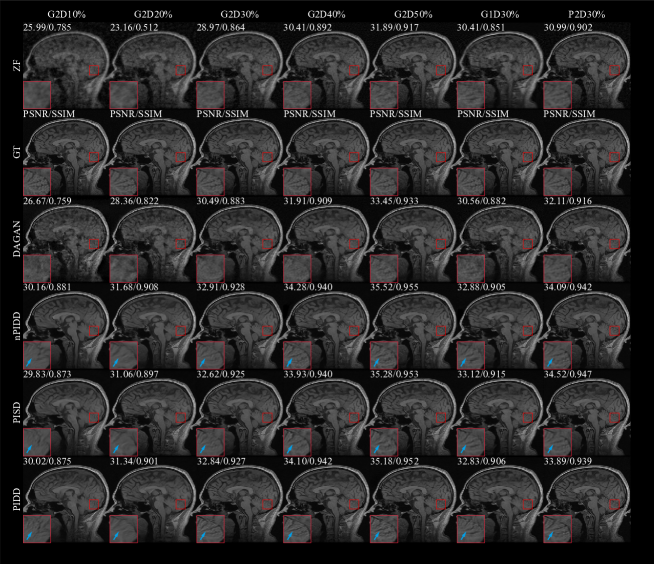

The testing result are shown in Fig. 7 and Fig. 8. Experimental results exhibit the same trend under all the different downsampling trajectories. The proposed method provides significant advantages for low downsampling percentage (high acceleration factor), with correspondingly significantly improved reconstruction quality.

The testing examples of the reconstruction are shown in Fig. 9. It can be seen from the results that PIDD has a significant recovery effect on edge information in the case of a low downsampling percentage (10–30%). The edge information of PIDD, particularly in sulci and cerebellum areas, is greatly preserved, compared to PISD. The texture details of PIDD are also richer than nPIDD. In the case of a high downsampling percentage (40–50%), the reconstruction problem becomes simpler, and the advantages of PIDD with enhanced reconstruction of edge information and the advantages of multi-channel data are less obvious. In the experiment of Gaussian 2D 50% undersampling, PIDD, PISD and nPIDD basically have the same quality of the reconstruction.